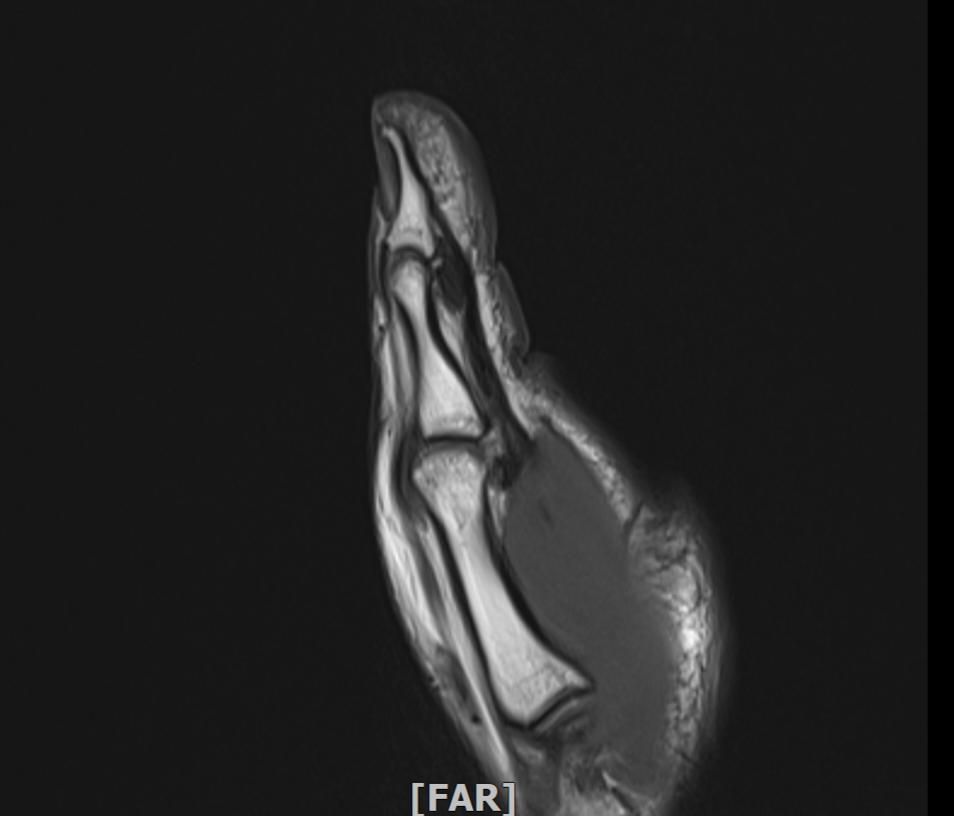

왼손 엄지손가락 부상 mri판독부탁드립니다

임팩에 장갑이 말리면서 엄지도 같이 말렸습니다

현재 손이 가끔 욱씬거리고 평소보다 뻣뻣하며 불안정감이 있는듯 합니다. mri사진으로 판독 가능하실까요 감사합니다.

정확한 판독을 하긴 어렵지만 연부조직의 주변부의 염증이 보여집니다.

올려주신 사진 상에서는 특별하게 큰 문제가 없을 수 있으나 부상과정에서 인대나 힘줄에 발생했던 부상으로 인해 긴장감이나 움직임 제한, 통증이 나티나는 경우에는 치료를 받아보시는 것도 좋겠습니다.

Mri 판독은 영상 전문의가 직접 이미지를 확인해야 정확하지만 엄지 부상 후 욱씬거림과 뻣뻣함, 불안정감은 인대 손상이나 골절, 건초염 가능성을 시사합니다. Mri에서는 인대 파열, 연골 손상, 골수 부종 등을 중점적으로 평가합니다. 증상이 지속되면 정형외과 전문의에게 영상 판독과 임상 진단을 반드시 받는 것이 안전합니다!